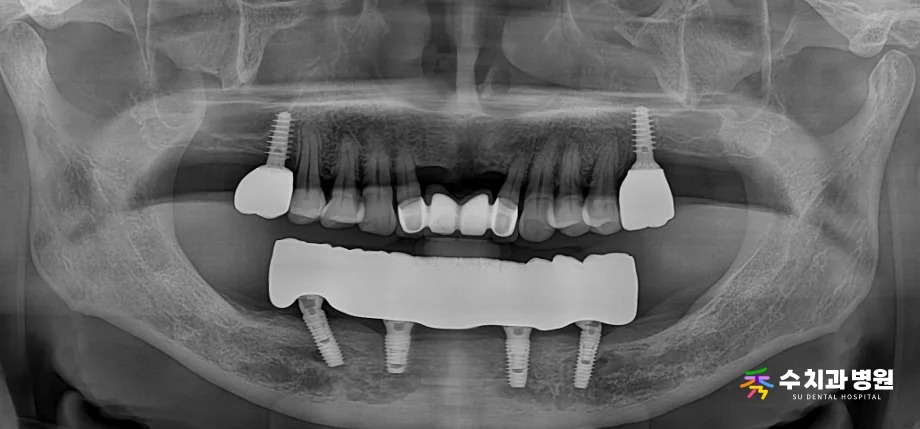

2️⃣ 임시 보철물 장착 및 적응

환자분의 약한 잇몸뼈 상태를 고려하여,

초기에는 플라스틱 재질의 임시 치아를 장착해

임플란트에 가해지는 힘을 점진적으로 늘려갔습니다.

[📸 치료 중 임시치아 사진] (촬영일: 2024년 7월)

[📸 치료 중 임시치아 엑스레이] (촬영일: 2024년 7월)

이 기간 동안 음식을 씹는 위치와 교합을 안정화하며,

환자분이 새로운 치아에 충분히 적응하실 수 있도록 도왔습니다.